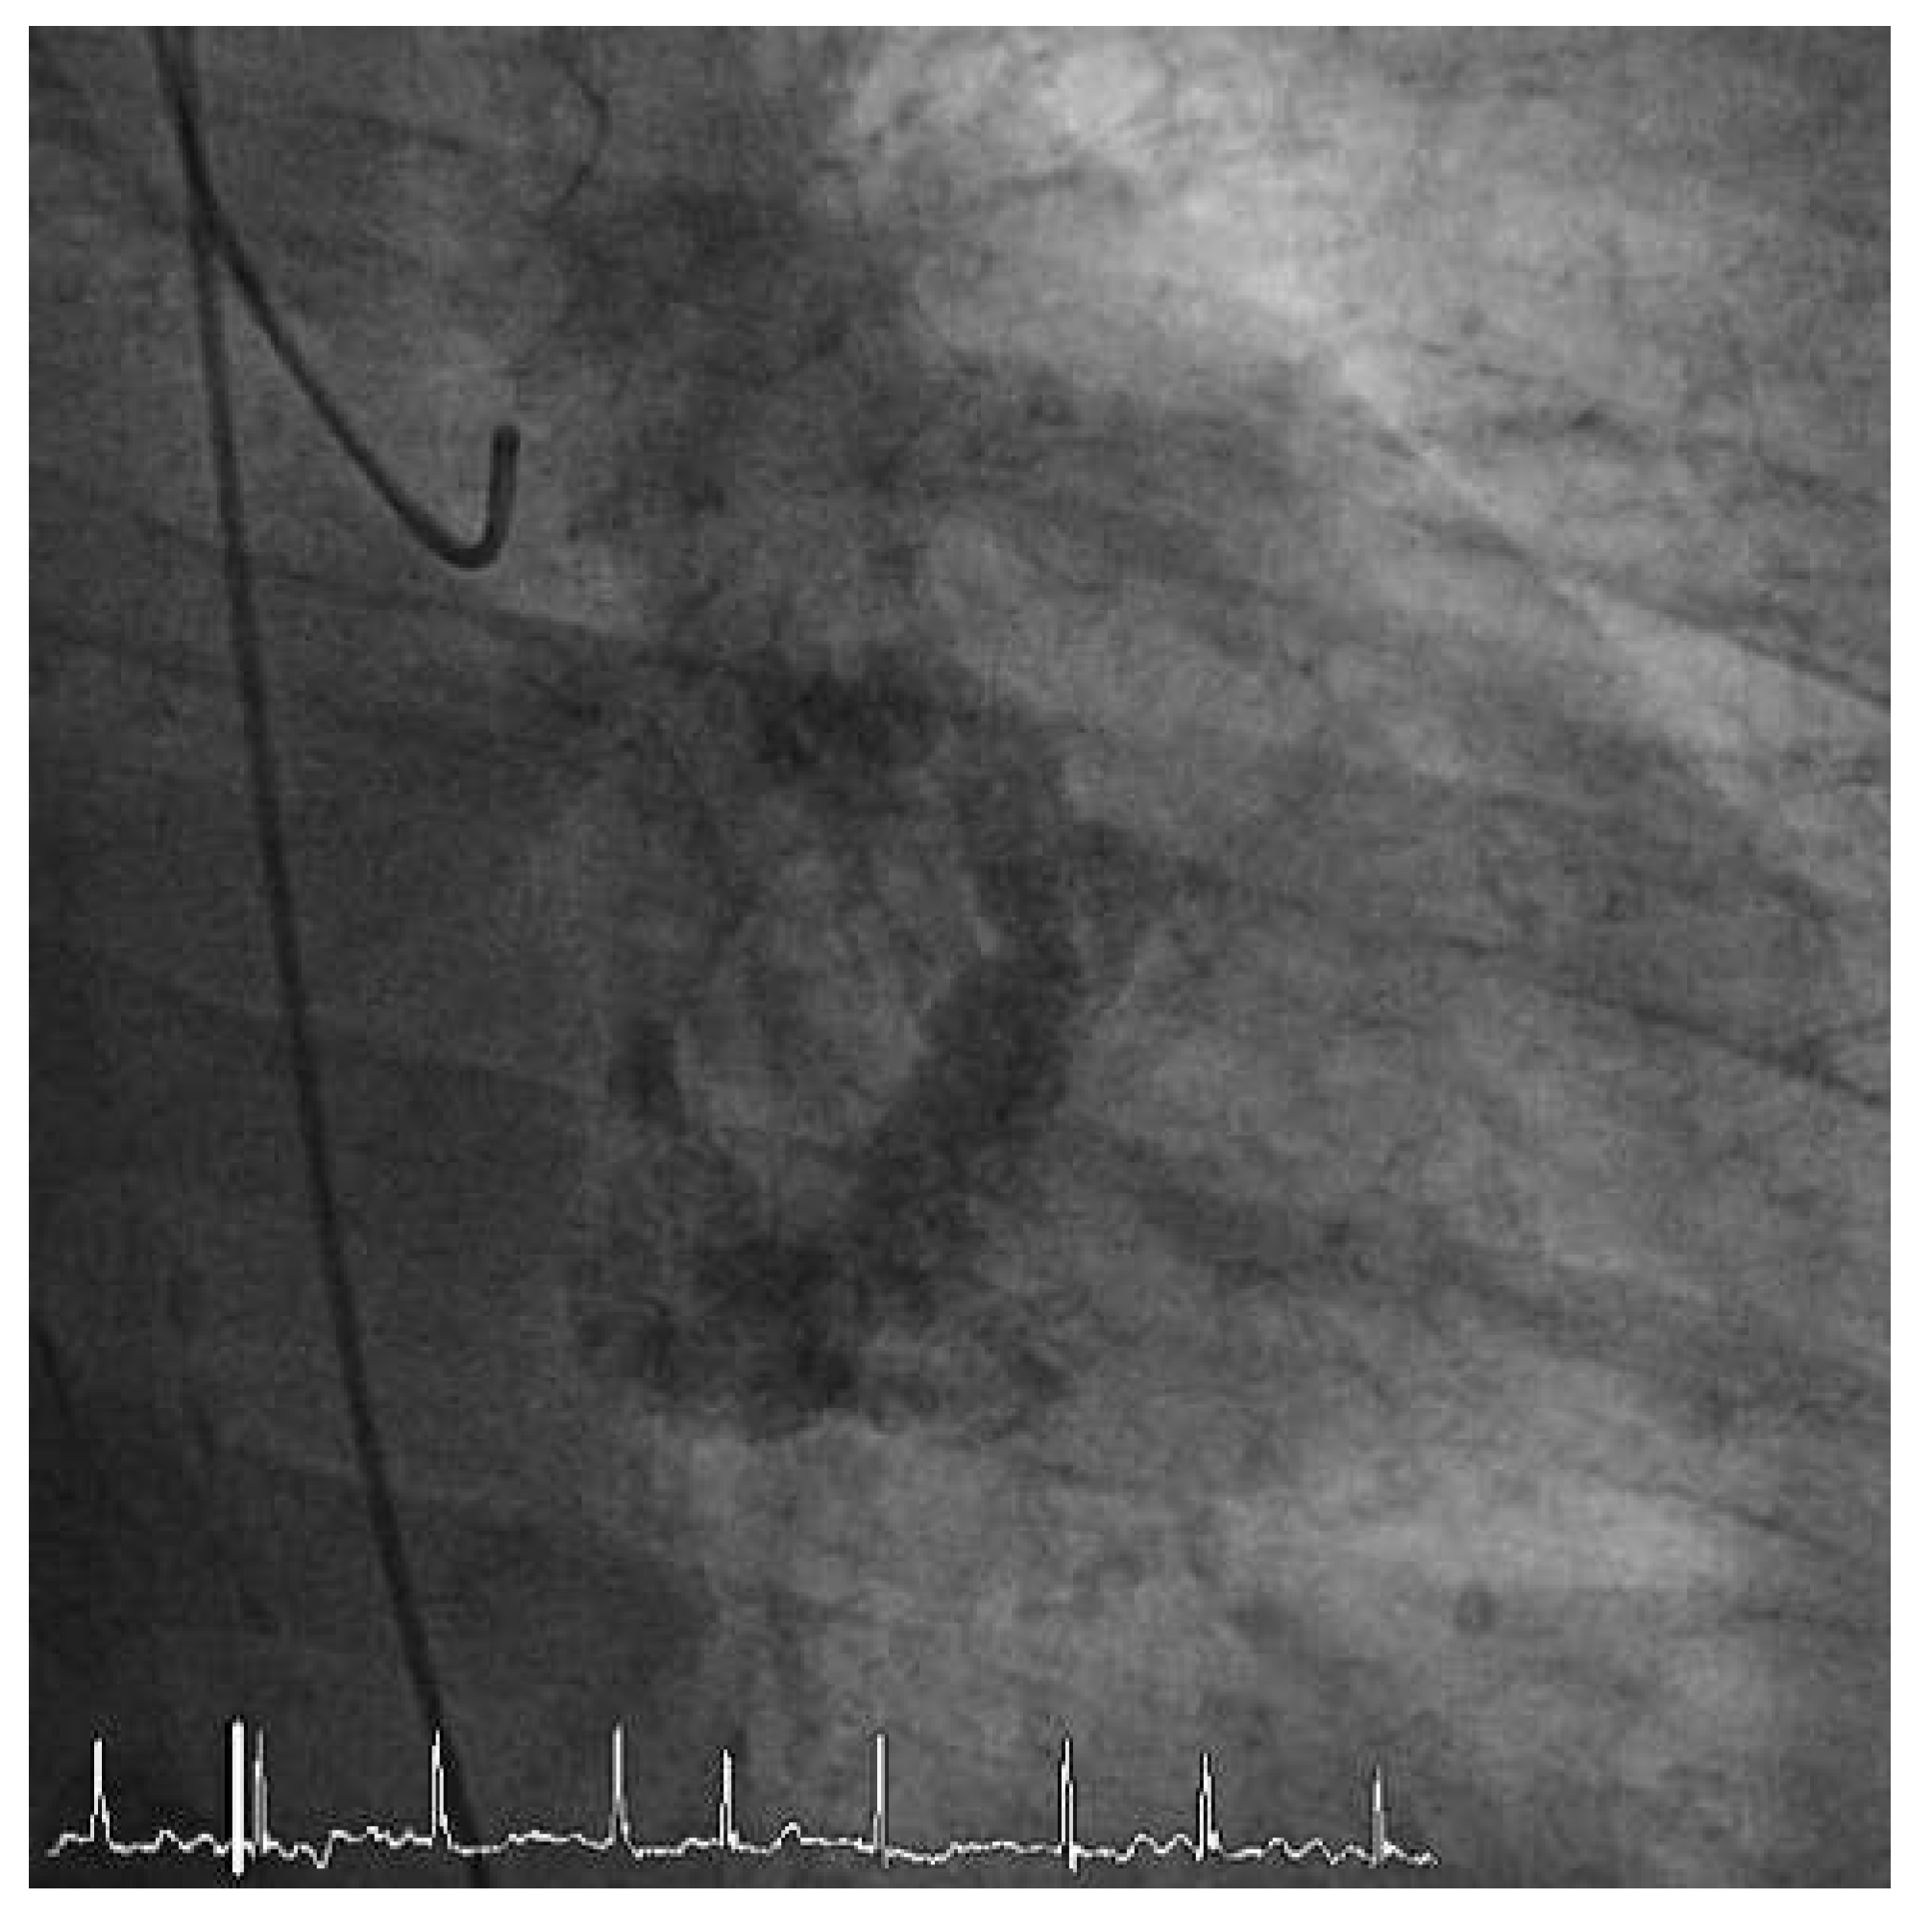

Worldwide First Surgical Implantation of a Transcatheter Valved Stent in Mitral Position

Case report